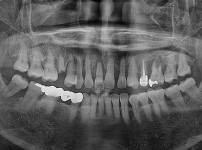

임플란트-전후사진1

치과를-선택할-때-꼭-확인하세요-서울숙면치과-임플란트-전후사진